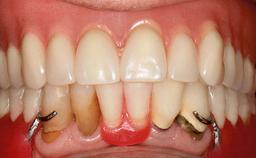

Mandibular Overdenture Supported by a CAD/CAM-milled Bar with Long Distal Extensions on Two Conventionally Loaded Implants

An 87-year-old man was referred to our Division of Gerodontology and Removable Prosthodontics at the University Clinics of Dental Medicine, Geneva, Switzerland for dental implant therapy. He was retired and led a very active social life, keeping himself busy in the company of his many grandchildren and with frequent travels to Italy. The patient’s past medical and drug histories revealed that he suffered from angina, asthma, and arthritis of the knee. He was allergic to penicillin. His regular prescription medications included anti-anginal and antiasthmatic drugs, along with occasional non-steroidal anti- inflammatory drugs for joint pain. Otherwise, he was a healthy patient who occasionally consumed alcohol on social occasions and did not smoke. A detailed dental history revealed that he had lost his teeth to chronic adult periodontal disease and had had an edentulous maxilla for over 20 years.